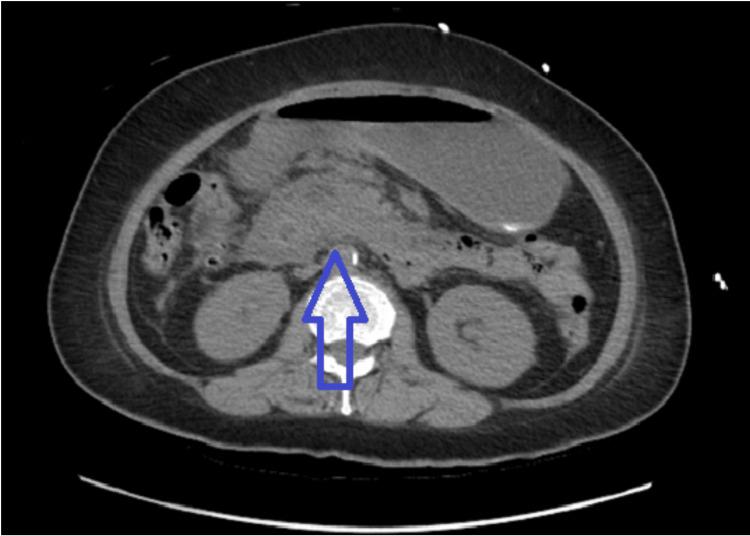

Euglycemic diabetic ketoacidosis (euDKA) is a life-threatening metabolic complication typically associated with type 1 diabetes mellitus (T1DM). However, its occurrence in type 2 diabetes mellitus (T2DM) remains exceptionally rare. We present a case report detailing the unusual manifestation of euDKA in a patient with T2DM following the initiation of treatment with a sodium-glucose cotransporter-2 (SGLT-2) inhibitor. The patient, a 67-year-old female with a history of T2DM and well-controlled blood glucose levels, was commenced on an SGLT-2 inhibitor as part of her antidiabetic regimen just two weeks prior. Subsequently, the patient developed euDKA despite maintaining near-normal glycemic levels. This paradoxical presentation challenges the conventional understanding of DKA in T2DM and underscores the need for heightened clinical awareness. EuDKA associated with SGLT-2 inhibitors is an infrequently reported phenomenon, further complicating the clinical landscape. This case contributes to the growing evidence suggesting an association between SGLT-2 inhibitors and the development of euDKA in patients with T2DM. The rarity of this occurrence necessitates a thorough exploration of potential risk factors and underlying mechanisms.

正常血糖性糖尿病酮症酸中毒(euDKA)是一种危及生命的代谢并发症,通常与1型糖尿病(T1DM)相关。然而,其在2型糖尿病(T2DM)中的发生极为罕见。我们报告一例病例,详细描述了一名T2DM患者在开始使用钠-葡萄糖协同转运蛋白2(SGLT-2)抑制剂治疗后出现的euDKA异常表现。该患者为67岁女性,有T2DM病史且血糖水平控制良好,仅在两周前开始使用SGLT-2抑制剂作为其抗糖尿病治疗方案的一部分。随后,尽管血糖水平维持在接近正常范围,患者仍发生了euDKA。这种矛盾的表现挑战了对T2DM中DKA的传统认识,并强调了提高临床意识的必要性。与SGLT-2抑制剂相关的euDKA是一种罕见报道的现象,进一步使临床情况复杂化。该病例为越来越多的证据提供了补充,表明SGLT-2抑制剂与T2DM患者发生euDKA之间存在关联。这种情况的罕见性需要对潜在风险因素和潜在机制进行深入探索。